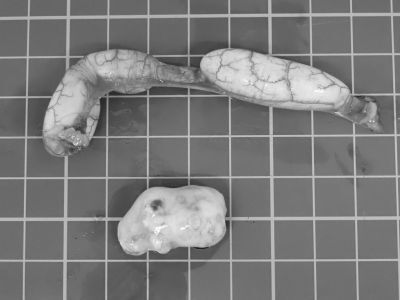

左右の卵巣と卵管を全て取り出し、お腹をしっかり洗浄して手術終了となりました。

ただ、意外なことに病理検査ではあまり炎症所見は認められず、「卵胞の変性、卵の閉塞」という診断でした。